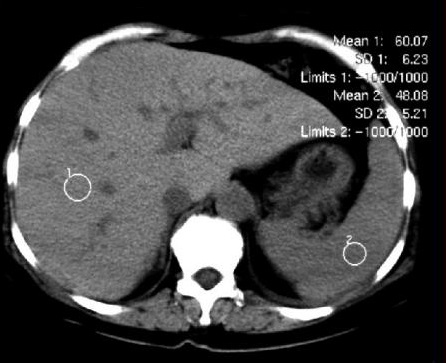

Image TDM de

steatose :

Normalement la densite du foie est

plus hyperdense de 6-12 UH que la rate . Par

infiltration de la graisse des cellules

hepatiques , la parenchyme devient fortement hypodense

( 30-40UH ) par rapport a une foie

normale ( normalement 50UH ) . Le foie est

steatosique quand sa densite en moindre 10 UH que la

rate . : |

Image TDM sans preparation :

Normalement la densite du foie 50UH et la rate est

40 - 45 UH . |

En cas steatose du foie la

densite du foie est moins dense 10UH que la rate |

Image TDM d'une steatose du

foie : Le foie est hypodensse que la rate . Gradient

normal sans injection foie/rate =10UH |